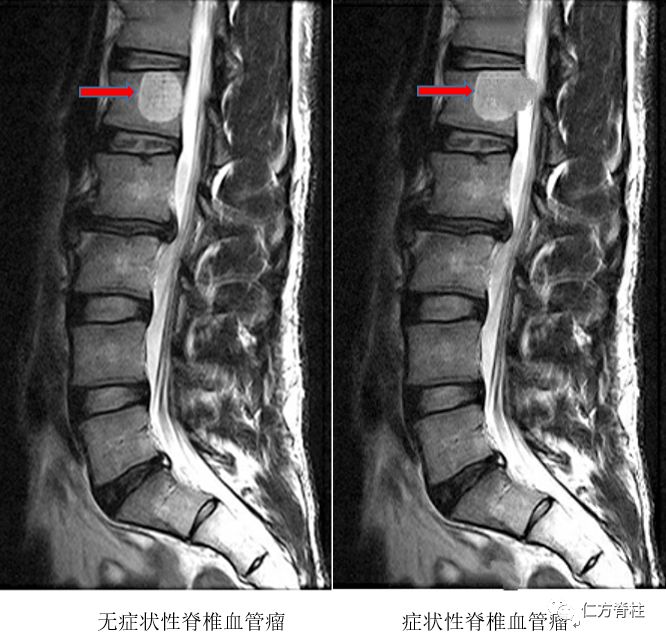

4球血管瘤 (glomangioma): 1)肿瘤界限不清; 2)血管多为扩张的海绵状血管,血管腔内可有血栓或静脉石形成; 3)球细胞簇少而菲薄; 5 球血管肌瘤 (glomangiomyoma): 1)由球细胞和平滑肌两种细胞成分围绕扩张的血管生长; 2)球细胞与平滑肌细胞相互之间骨血管瘤由骨內正常內皮細胞被覆的血管所構成,骨血管瘤多數情況下是血管的錯構瘤,也有一部分是真正的腫瘤,如近年來觀察到的上皮樣血管瘤。 骨血管瘤是常見的良性骨腫瘤,佔所有骨腫瘤的 1%,約有 10% 的人群有無症狀性的椎體血管瘤。Oct 22, 09 · 骨血管瘤是一種呈瘤樣增生的血管組織,摻雜于骨小梁之間,不易將其單獨分離。從組織學上分為海綿狀血管瘤及毛細血管瘤,前者多見於脊柱和顱骨,後者多見於扁骨和長管骨幹骺部。

脊柱血管瘤 血管瘤 疾病介绍